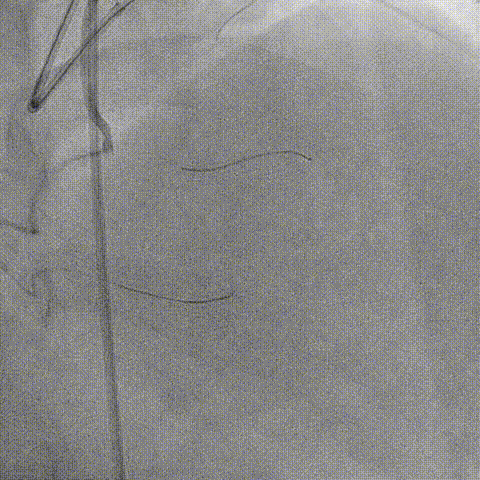

RCA中段重度迂曲、逆向联合Expressman与Mamba,因血管迂曲 Sion无法操控,换用Suoh 03通过间隔支进入LAD

Mamba无法通过侧枝血管、深插Expressman、微导管至LAD中段、逆向先后尝试Judo 1, Judo 3, Judo 6, Gaia 3, CP 12

因血管钙化严重、导丝前进困难